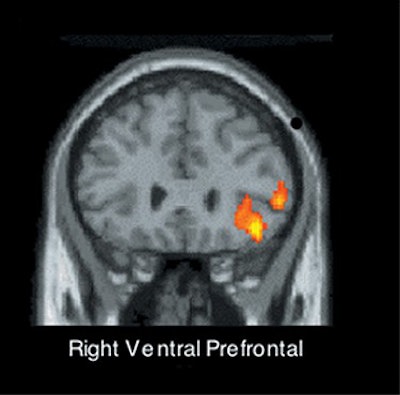

The areas in question are the anterior cingulate cortex (ACC) and the right ventral pre-frontal cortex (RVPFC), Eisenberger said.

The RVPFC, on the other hand, seems to act as a governor, partly regulating the ACC and easing the feeling of pain when it’s active, Eisenberger said.

Subjects who were most upset about the snub had the highest level of activity in their ACC. Conversely, those who were least upset had high activity levels in their RVPFC, Eisenberger said.

![]() |

| Subjects whose right ventral prefrontal cortex was more active reported less distress from exclusion. Images courtesy of Naomi Eisenberger and Matthew Lieberman, Ph.D. |

The pattern of activity was "very similar" to that seen in studies of physical pain, she said, implying that the two types of discomfort share a common anatomical basis.